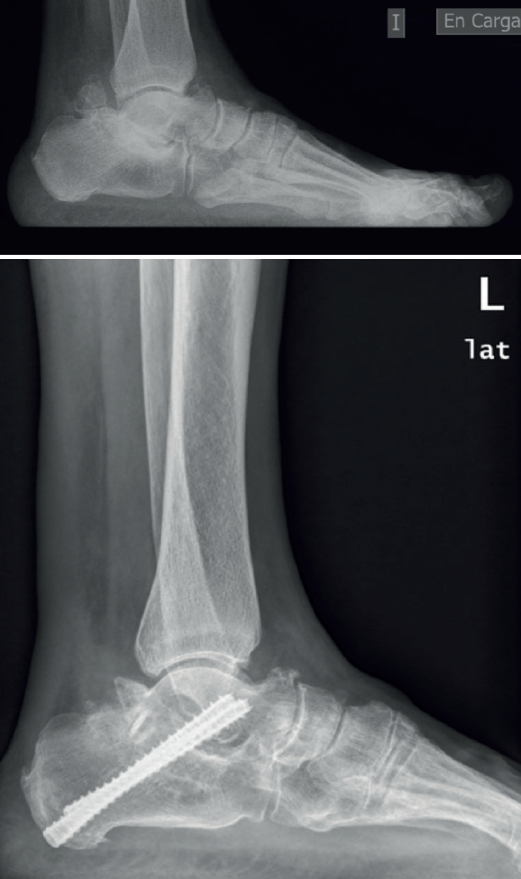

Hemos planteado en algunos de estos casos la artrodesis subastragalina por vía posterior, utilizando el propio osículo como autoinjerto (Figura 9), junto con artroscopia de tobillo por vía anterior sin resultados concluyentes por el momento y que precisan ser analizados a más largo plazo.

En aquellos casos con masa ósea considerable, como consecuencia de os trigonum gigante, talus bipartitus o síndrome de Trevor, se produce a lo largo del tiempo una listesis posterior de esta, con la consiguiente basculación del cuerpo del astrágalo, produciendo en el adulto artrosis subastragalina posterior y choque tibioastragalino anterior con formación de osteofitos y limitación dolorosa de la movilidad.